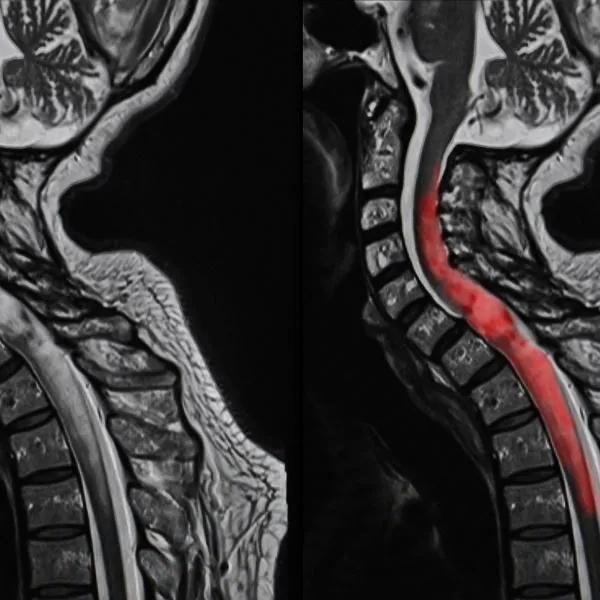

elderly neck pain

โรคกระดูกคอเสื่อม